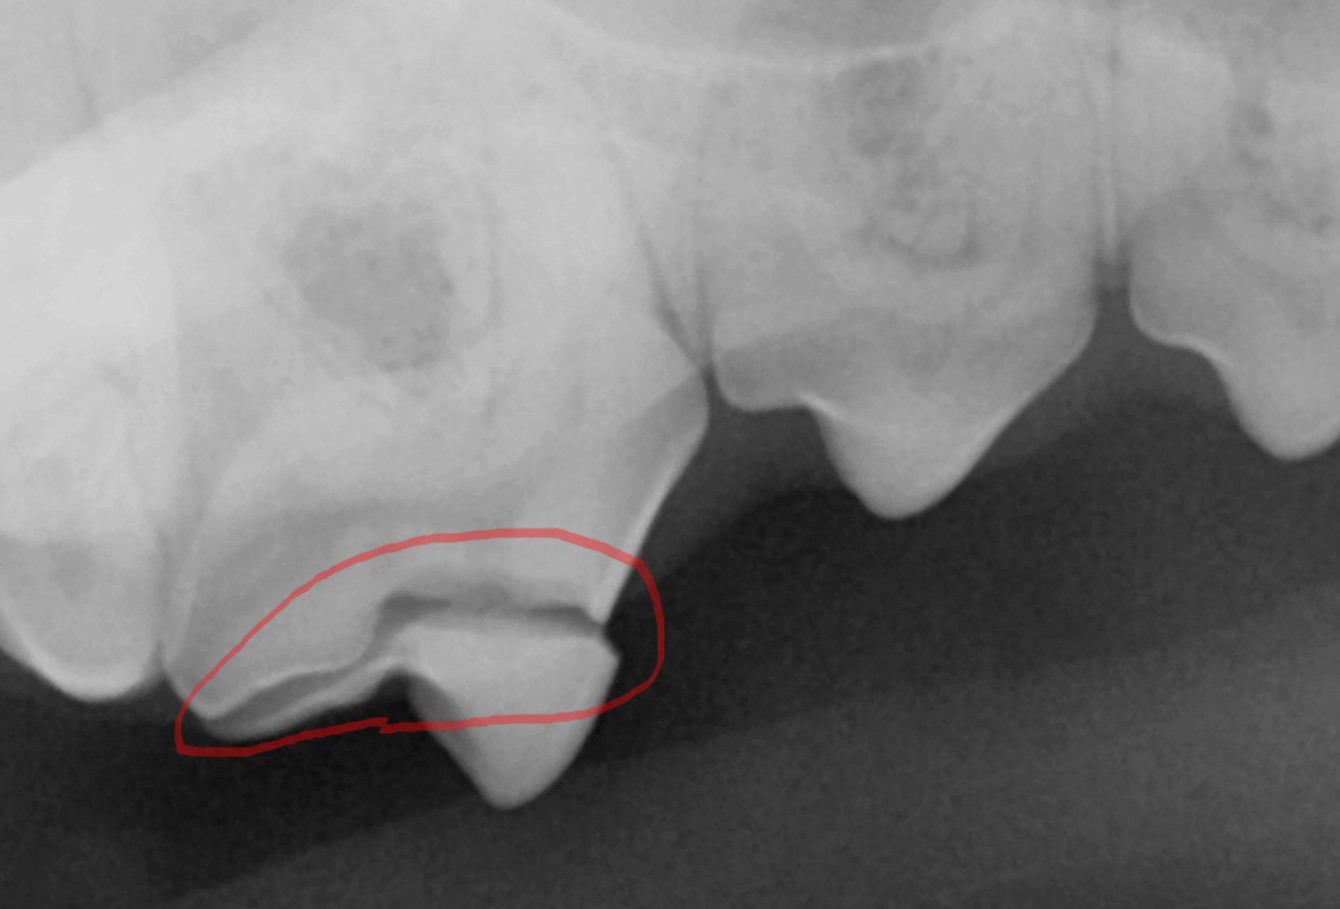

엑스레이 촬영 결과도 같은 부위에서 방사선 투과선이 명확히 관찰되었습니다.

치관의 법랑질과 상아질 경계를 따라 이어지는 이 선은 단순 표면 손상이 아니라 치수강 바로 인접한 손상으로 확인되었습니다.

엑스레이 결과, 우측 상악 제4전구치(p4)는 법랑질과 상아질이 함께 손상된 복합 치관 파절로 확인되었습니다. 치수강 근처까지 금이 이어져 있어 보존 치료는 불가능했기 때문에, 결국 수술적 발치를 진행하기로 결정했습니다.